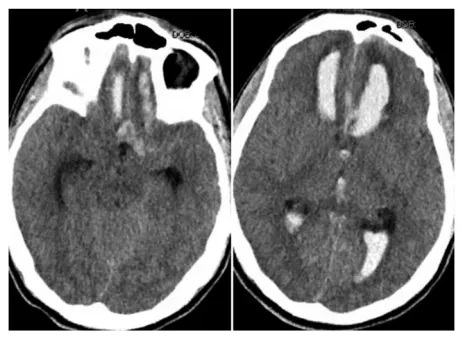

病因最终明确位于颅内:急诊CT检查(图1)显示前交通动脉动脉瘤破裂,伴发大面积脑实质出血、蛛网膜下腔出血及脑室内出血,同时发现左侧鞍旁段颈内动脉存在小型未破裂动脉瘤。手部伤痕经检查推断为夜间昏迷期间遭小型动物啃咬所致。

(图1:前交通动脉瘤破裂引发广泛脑实质、蛛网膜下腔及脑室内出血的CT影像表现)